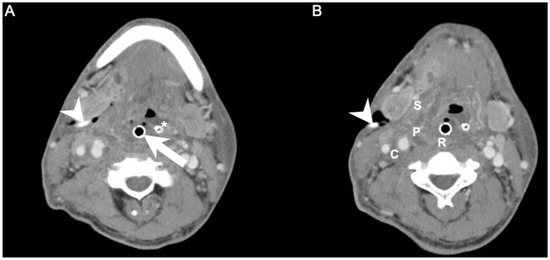

We retrospectively reviewed the medical records of 605 patients with DNIs who were admitted to Chang Gung Memorial Hospital (Linkou, Taiwan) between July 2016 and February 2022. DNI was diagnosed by ultrasonography and computed tomography (CT) [7]. The involved deep neck spaces of CT images were identified retrospectively by at least one radiologist (S.-C.C.) and one otorhinolaryngologist (S.-L.C.). If there were situations where the involved deep neck spaces were difficult to identify, it would be decided by team discussion. Treatment included antibiotics and surgical incision and drainage (I&D). I&D was performed when the DNI compromised the airway, the abscess was large (≥2 cm), and when the DNI did not improve after 48 h of intravenous empirical antibiotics [16]. These antibiotics were ceftriaxone 1 g/12 h and metronidazole 500 mg/8 h; they reduced the levels of aerobic and anaerobic bacteria before culture results were available [17,18]. Postoperative irrigation was performed at intervals of 4–8 h depending on disease severity [19]. Repeat I&D was defined as more than one drainage procedure during the same hospital stay. We followed the patient’s clinical condition and laboratory data after the first open I&D. If the patient’s symptoms and data progressed seriously within 48–72 h, we further arranged a CT exam. If there were abscesses that must be drained, the clinician would arrange a repeated open I&D (Figure 1A,B).

Figure 1. (A,B). Axial views of a patient who required repeat I&D. Arrowhead: drainage tube of the first surgery; Arrow: endotracheal tube; Asterisk: nasogastric tube; C: carotid space; P: parapharyngeal space; R: retropharyngeal space; S: submandibular space.